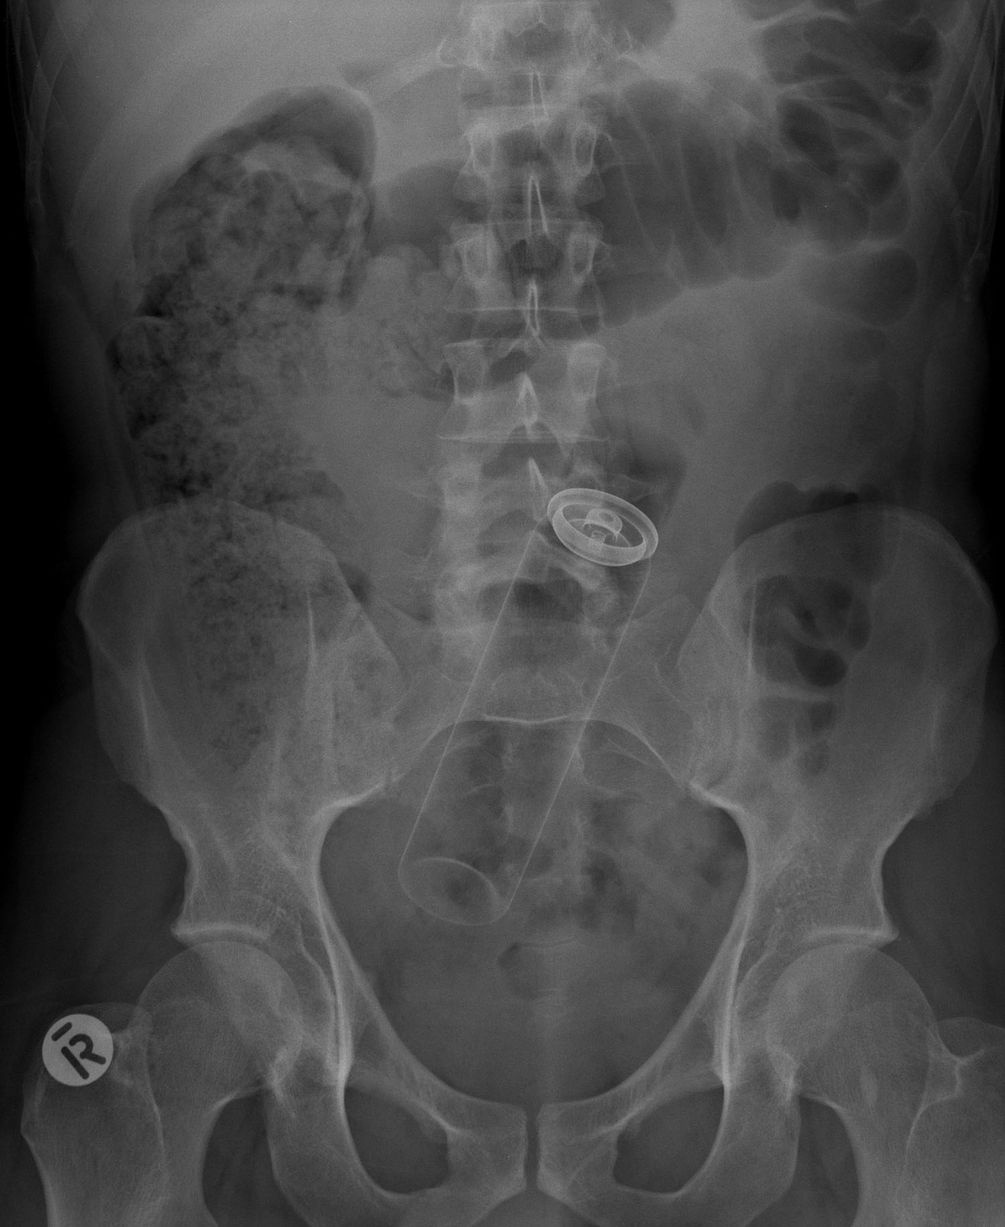

Đồ chơi phát sáng trong ruột một người.

Đồ chơi mô hình trong ruột một người.

Điện thoại iPhone trong ruột một bệnh nhân.